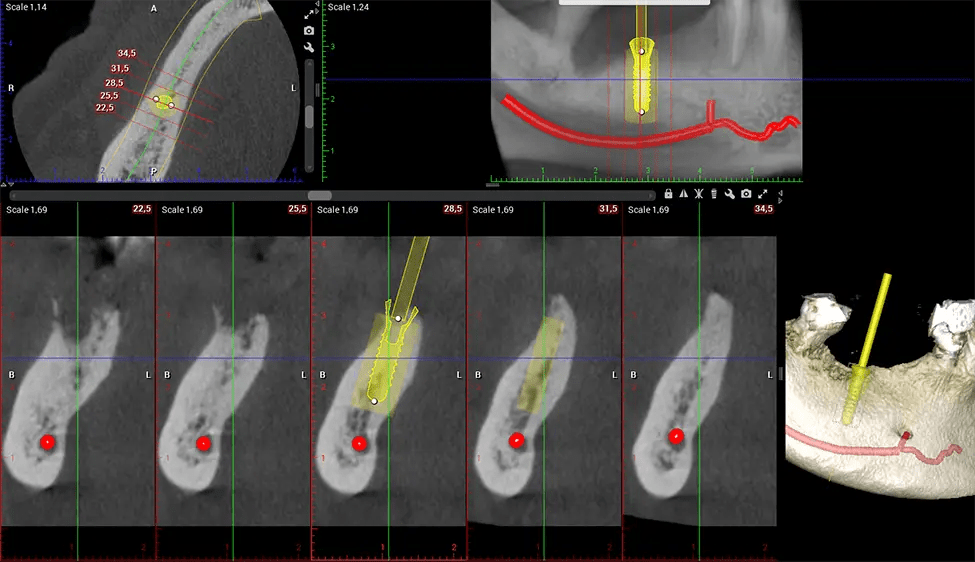

Another significant benefit is that 3D imaging provides more precise images of your bone structure. These images are more detailed, providing you with a more accurate diagnosis. An accurate diagnosis means better treatment for you.

When paired with extractions, dental implant placement, or bone grafting, CBCT technology can provide you with a quicker and much more comfortable experience. This is because the 3D image provides a more detailed picture of your entire oral cavity, allowing your dentist to walk you through each step of the process before it occurs. This often helps patients feel more prepared and comfortable overall, especially if they have had a traumatic experience with past dental treatments.

After the scanning process, the captured X-ray images are processed by the CBCT software, which applies algorithms to reconstruct a detailed 3D image of the scanned area. The software compiles these individual X-ray images and creates a digital 3D representation of the patient’s anatomy. The reconstructed 3D CBCT image can be viewed and analyzed by the dentist or radiologist. This image can be manipulated, rotated, and zoomed in or out to examine specific structures and evaluate the patient’s condition.